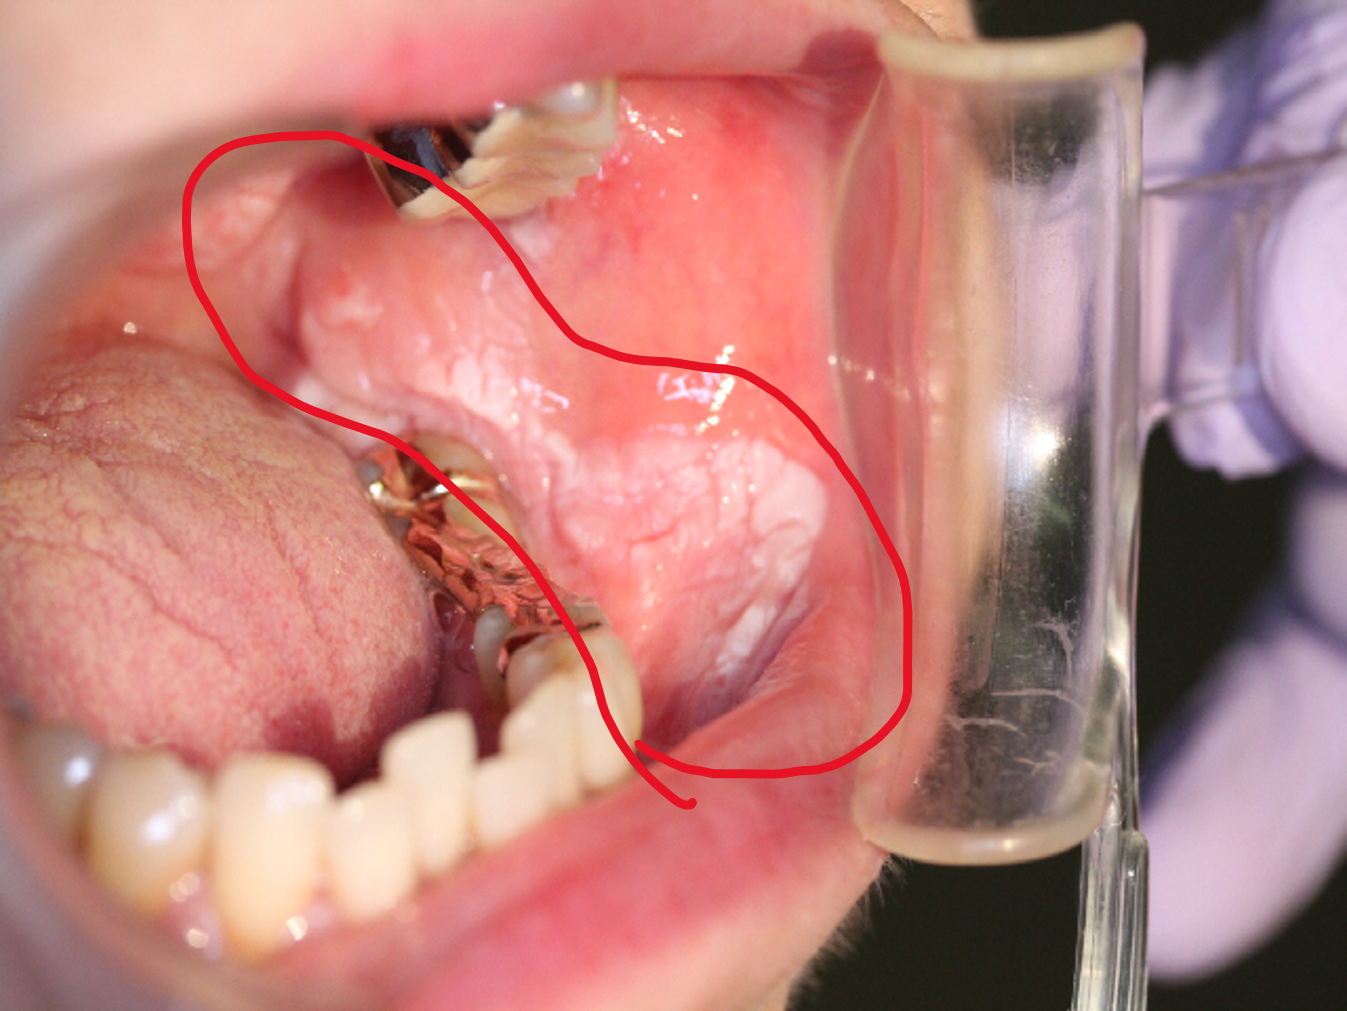

口腔がんでは、がんができた部分の粘膜が赤くなったり、白色に変色したり、形が変わったりします。口の中に硬いしこりや腫れができることもありますが、初期にはほとんど痛みや出血を伴わないため、口内炎と思い込んで、そのまま放置してしまうケースも少なくありません。2週間しても口内炎がなかなか治らないような場合は、注意が必要です。

口腔がんでは、粘膜の赤色や白色への変色やただれ、しこりのほか、刺すような強い痛みを伴うこともあります。進行すると口が開けにくい、食事が飲み込みにくい、話しにくいなどの様々な症状があらわれます。あごの下や首筋にできた無痛性のしこり(リンパ節)はリンパ節転移である可能性があるため、要注意です。

口腔がんの前がん病変である「口腔白板症」とは?

白板症は、舌や歯肉、頬粘膜などによくみられる白斑状のざらざらした病変で、この病変の約3~14.5%は、将来がん化するといわれています。こうした前がん病変(細胞が現状ではがんとはいえないが、将来がんに進行する確率が高い状態)としては、紅色(赤色)のつるっとした病変が特徴の紅斑症(紅色肥厚症)もあります。